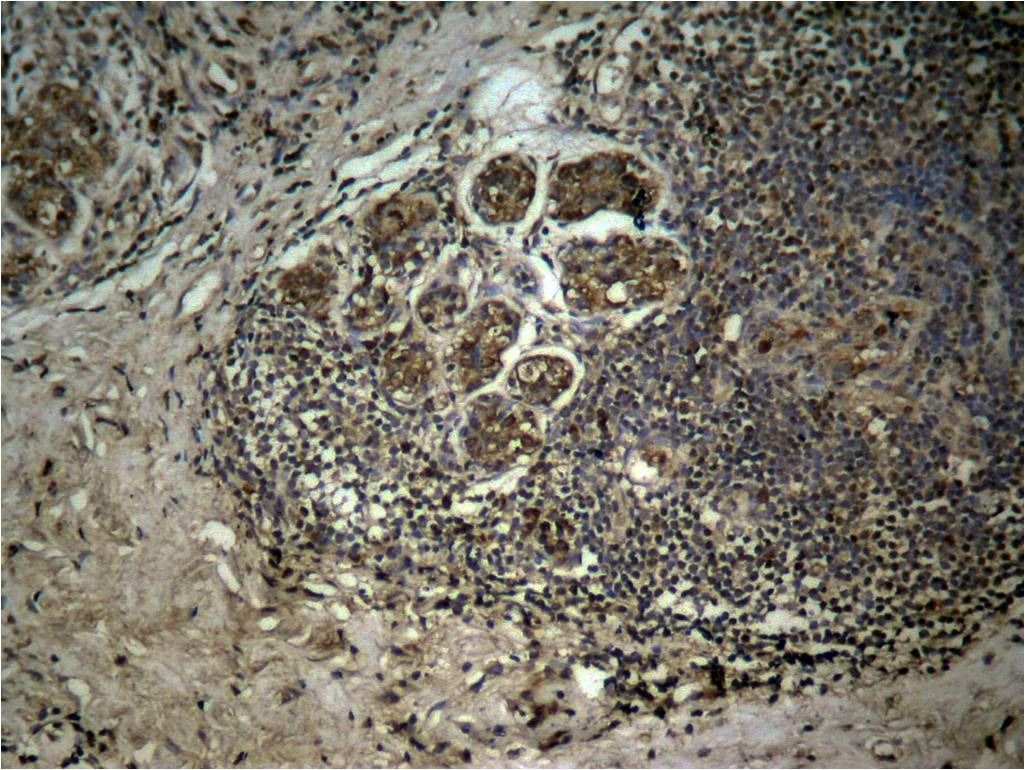

| Verified Activity | 1. Western blot analysis of extracts from HT29 and C6 cells using Histone H3 (Tri-Methyl-Lys27) Antibody TMAC-01910. 2. Immunohistochemical analysis of paraffin-embedded human breast carcinoma tissue using Histone H3 (Tri-Methyl-Lys27) AntibodyTMAC-01910. 3. Immunofluorescence staining of methanol-fixed MEF cells using Histone H3 (Tri-Methyl-Lys27) Antibody TMAC-01910. ![]() ![]() ![]() |